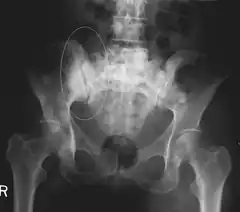

Sclerotic breast cancer metastases in the pelvis.